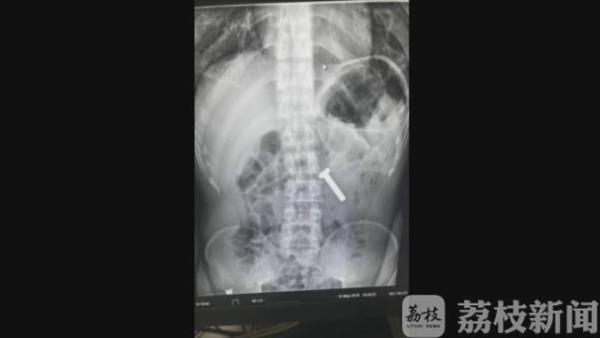

办案民警随赶紧将赵某带到医院做胃镜,发现他竟然生吞了一枚铁质螺丝钉,长约两厘米。原来,赵某曾经因为盗窃、吸毒等违法犯罪行为,被多次打击处理,深知警方办案流程。

据赵某交代,他了解到警方在关押犯人时,如果嫌疑人体内有异物,看守所是拒收的,这样他就能顺利变更强制措施为取保候审。事后,医生顺利的从赵某胃中,取出了这枚螺丝钉,赵某的计划落了空。